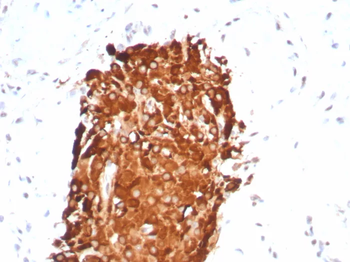

IHC analysis of formalin-fixed, paraffin-embedded humantesticular carcinoma. Staining withrINHA/6919at 2 ug/ml in PBS for 30 min RT. HIER: Tris/EDTA, pH9.0, 45 min. 2°: HRP-polymer, 30 min. DAB, 5 min.